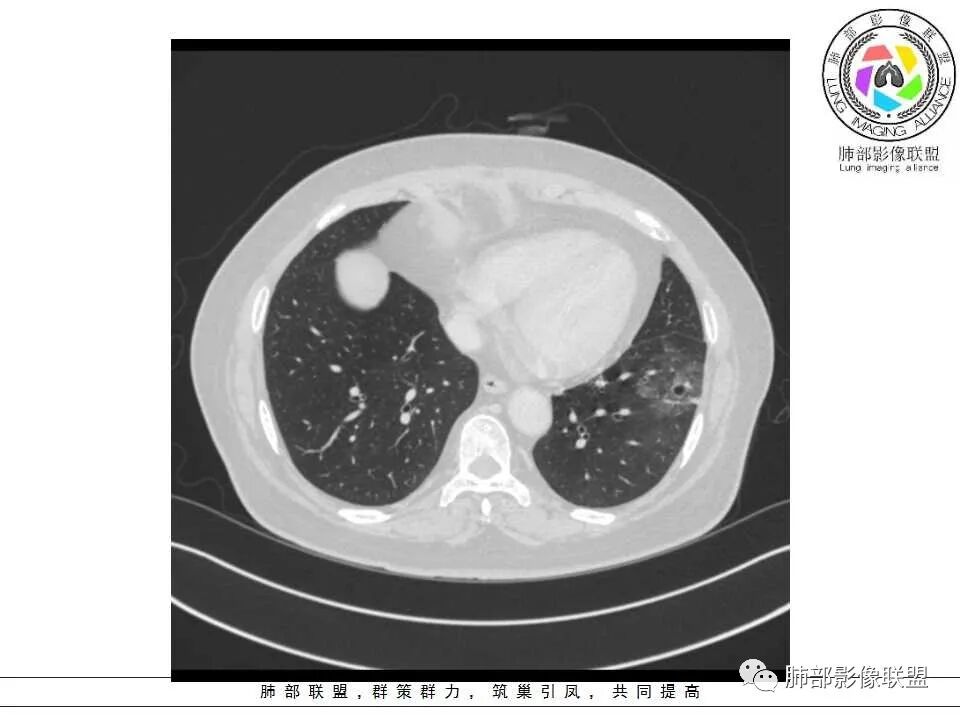

患者,女,65岁,2月余前受凉感冒后开始出现咳嗽,咳白痰,初发热2天,体温38℃左右,后降至正常,咳嗽无好转。近2日咳嗽加重,痰量增多,为黄白痰,无发热,无乏力、盗汗,无胸痛、胸闷,无头晕、头痛,无恶心、呕吐。PET-CT检查提示炎性病灶与恶性结节鉴别困难。

病灶分两部分

周围大片GGO

中央囊实性病变

南边:

病史没提咳血,周围出血灶似乎不太好说

部分边界偏清

囊腔有张力,外形有分叶,壁厚薄不均,有间隔,有强化

哪些病变可能?

1、癌

2、炎性:曲霉菌?

3、良性:囊腺瘤样畸形合并感染

患者老年女性,2月前受凉后出现发热,咳嗽咳痰,痰量增多,无咳血,病程较长,临床症状无明显好转并,近2日咳嗽加重,痰量增多,为黄白痰,无发热,无乏力、盗汗,无胸痛、胸闷,无头晕、头痛,无恶心、呕吐。

影像特点:

1、左肺下叶外基底段不规则囊腔样病灶,囊腔内有条形影及血管穿行。

2、囊壁薄厚不均匀,稍显僵硬,有壁结节(对应边缘分叶等)、结节强化明显。

以上两条几乎将肺囊肿彻底排除在外,且高度怀疑新生物!

3、灶周环以大范围磨玻璃影,非常均匀,没有重力分布趋势,分叶状,边界隐约可变。

4、冠状位部分层面可见支气管在囊腔边缘截断。